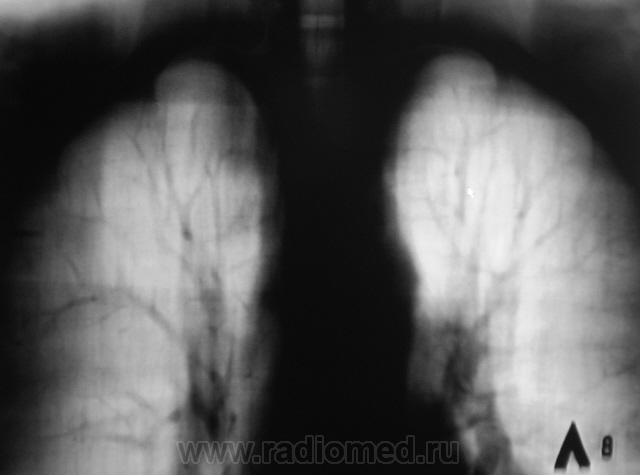

Я, конечно, не все срезы выставил, но после "семерки" - фавора тубарского, все дружно "глотнули" слюну, которая накопилась в яростном споре, и во всем опять обвинили "флюору", мол - де - "предел флюры"...

Сеучас семерку выставлю.

"Семерка".

Продолжение.